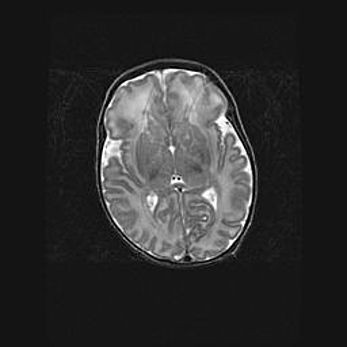

Неполная лизэнцефалия (пахигирия). Открытая гидроцефалия.

Возраст: 17 дней

Вес: 3110 г

Пол: мужской

Окружность головы: 33,5 см

Срок гестации: 35-36 недель

Лизэнцефалия—недоразвитие корковой пластинки и мозговых извилин в результате нарушения миграции нейронов коры. Поверхность мозговых полушарий гладкая. Микроскопически выявляется отсутствие нормальных слоев коры и скопление групп нейронов в подкорковом белом веществе.

Пахигирия—уменьшение числа вторичных извилин. В пораженном полушарии нервные клетки образуют толстый недифференцированный слой с неправильно расположенными нервными волокнами и группами гетеротопных клеток. Нервные клетки незрелые. Белое вещество истончено. При этом нередко аномально развит корково-спинномозговой путь.